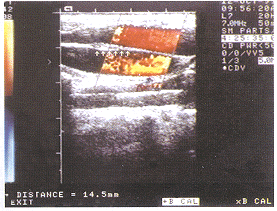

患者男,11岁。无意中发现右侧颈部屏气后隆起而来诊。体检:患儿屏气后可见右侧颈部局部隆起,触之柔软、囊性感,未触及搏动及震颤,临床诊断:右侧颈内静脉扩张。彩超检查:右侧颈内静脉局部呈梭形扩张,扩张段长约30mm,扩张内径:平静呼吸为14.5 mm,屏气后为19.7 mm,其扩张段静脉内可见一带状强回声分隔(图1),将扩张段分为内外两个管腔,分隔长约36mm,一端游离(图2)。CDFI:内外两个管腔血流速度不同,内侧快于外侧。左侧颈总静脉内径:平静呼吸为7.2mm,屏气后为9.3 mm,血流未见异常。彩超诊断:右侧颈内静脉扩张并重复畸形,左侧颈部静脉未见异常。行阔筋膜扩张静脉包裹术,术中见颈内静脉被分隔为内外两个管腔,屏气后两个管腔均扩张。

图2 分隔游离端